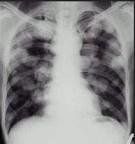

问题 男,45岁,HBV阳性十年,胸痛1月伴咳嗽,咯血1天,胸片如图,选择最可能的诊断()

选项 A.肺多发性脓肿 B.肺韦格氏肉芽肿 C.HBV病毒肺部转移 D.金葡菌感染 E.肺转移癌

答案 E